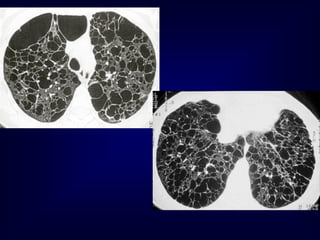

• Cigarette smoking •Ageing (presbyteric) lung “expected” changes

• 97.

• 98.

• 99.

• 100.

• 101.